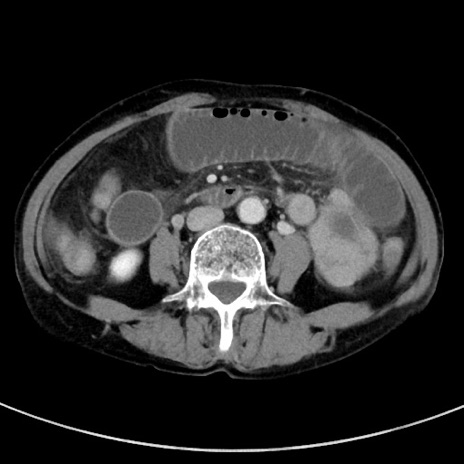

症例23(横断像)

【症例】70歳代女性

【主訴】下腹部痛・嘔吐

【現病歴】2日前より腹痛あり。昨日嘔吐あり。症状改善しないため来院。

【既往歴】胃GISTに対して胃部分切除後。

【身体所見】BT 37.1℃、BP 128/77mmHg、腹部:平坦・軟、下腹部に圧痛あり。

【データ】WBC 10200、CRP 0.31